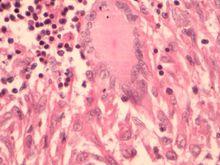

經過瑞氏染色的朗罕氏巨細胞,是多核巨細胞的一種,體積大,胞漿寬,漿著粉紅色,胞核從十幾個可達近百個,如類上皮的核,核染色質較疏鬆,核膜較厚,著紫紅色。核常沿邊緣分布。朗罕氏巨細胞是結核病中的典型細胞。